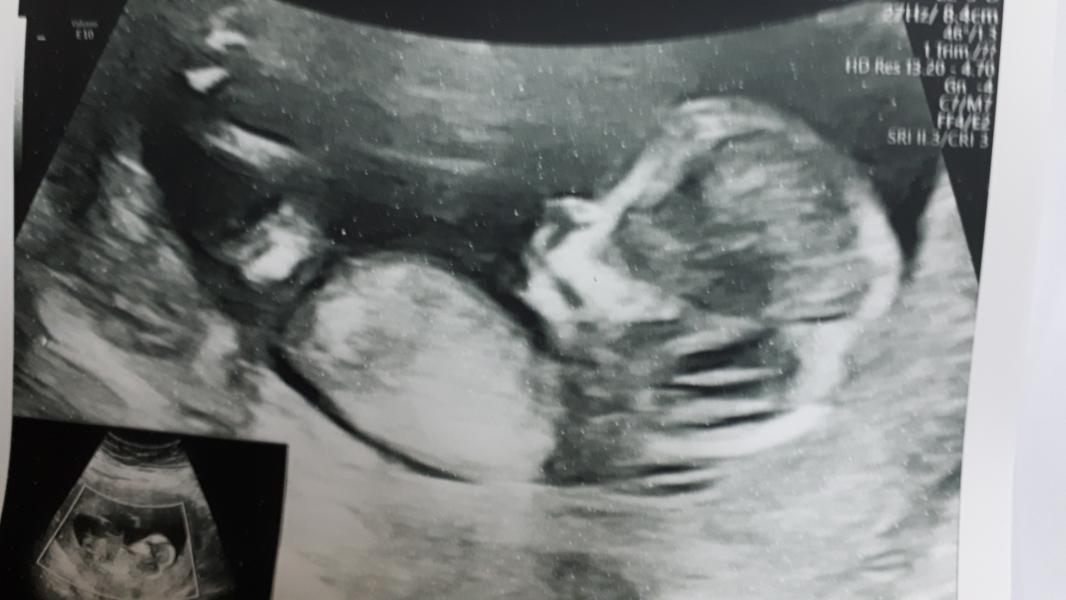

21 октября первый скрининг.

А еще у нас ДЕВОЧКА!!! 😍😍😍После двух мальчиков это конечно радость💗💗💗 узи проводила Батурина И.В.

По узи пдр ставят 05.05.20 по месячным 30.04.